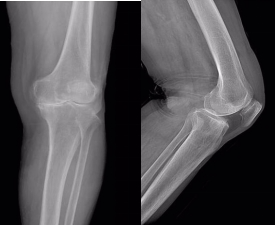

今年 85 岁高龄的姬奶奶、75 岁的孙爷爷均患有多年严重的膝关节骨性关节炎,起初以为适当休息就可缓解疼痛;然而,随着年龄的增长,膝关节疼痛的愈发加剧,经辗转多家医院寻求保守治疗后,症状缓解不明显,近期自觉膝关节疼痛难忍、无法正常行走,严重影响了生活质量,听闻延安市中医医院正在开展「春雨行动」-骨关节置换手术援助公益行活动,遂在家人陪同下,不约而同地来到骨科门诊完善检查、评估病情后报名参加了第六批公益活动。

入院后,北医三院驻延专家、骨科主任姜宇组织科室集体讨论,并邀请北京大学第三医院关节外科专家团队远程会诊,结合影像学资料,完善相关化验检查,排除了手术禁忌症后,为他们设计了详尽、周密的手术治疗方案。

术前准备完善后,北京大学第三医院关节外科专家李杨副主任医师来到延安为两位患者先后实施了左侧人工全膝关节表面置换术。术中见膝关节软骨磨损严重,克服了因下肢力线与畸形、骨质缺损、骨骼质量、肌肉萎缩、关节强直等引起的种植体的准确放置、韧带间的平衡和肢体对线的恢复等诸多难题,为他们顺利植入了仿生的人工假体。